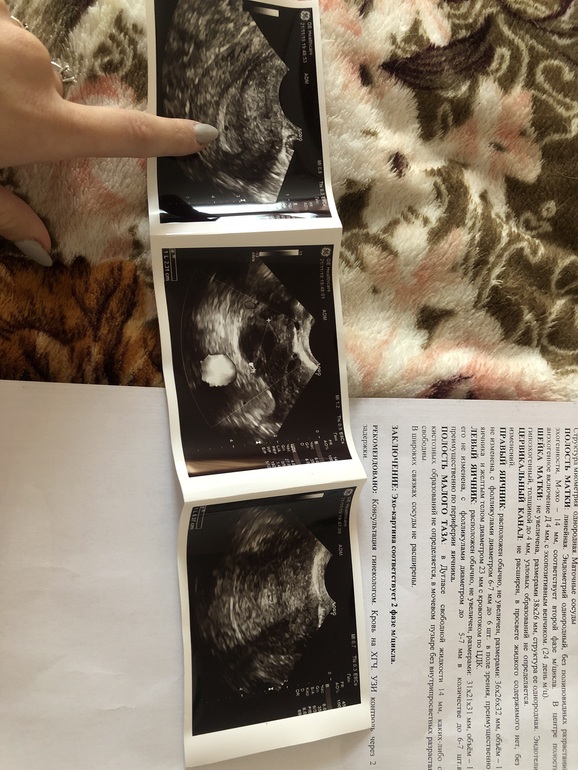

И вот фото приложила , что узостей написал и видно на другом фото чёрную точечку 4мм

Анэхогенное включение что-то великовато для хгч 10, но это еще не значит, что Б нет, мне кажется. Все правильно написали в заключении. По поводу этого включения, надо переделать узи еще раз, по поводу развития Б еще раз сдать хгч.

Во время беременности матка должна быть увеличена и полость матки при беременности рыхлая, а у вас ни того ни другого нет. У меня уже трое детей и у двух сестёр тоже по трое деток, так что судя по УЗИ у вас беременности нет, и это точно

Куда поставила палец там чёрная точечка и узисит написала об этом